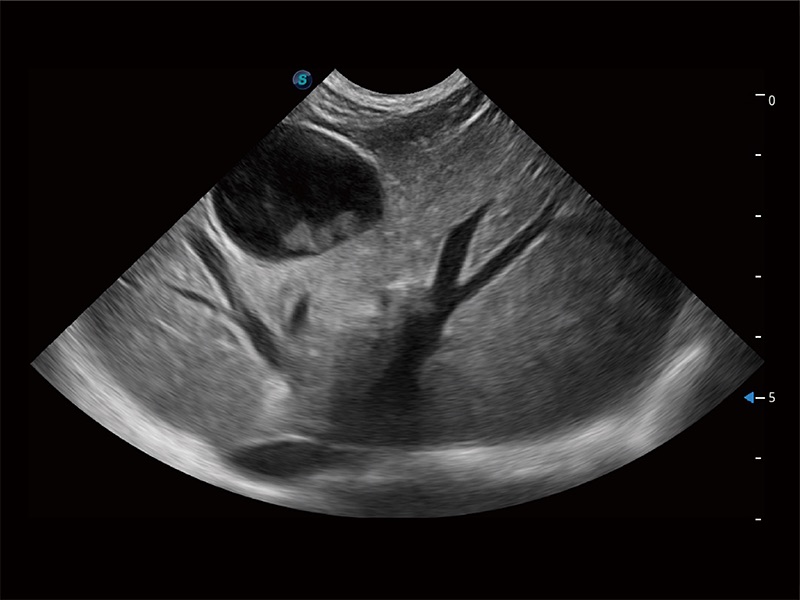

高性能和先進(jìn)的臨床應(yīng)用工具可以為動(dòng)物醫(yī)生提供臨床信心。ProPet 80 搭載了先進(jìn)的腹部和淺表應(yīng)用工具,幫助醫(yī)生在日常臨床實(shí)踐中發(fā)揮前所未有的作用。

ProPet 80 專為動(dòng)物醫(yī)生設(shè)計(jì),對(duì)不同的動(dòng)物體型和生理結(jié)構(gòu)作出了針對(duì)性的優(yōu)化。通過(guò)動(dòng)物影像專用軟件,可滿足個(gè)性化的應(yīng)用需求,幫助動(dòng)物醫(yī)生獲得更精確的診斷數(shù)據(jù)。

ProPet 80 全新的動(dòng)物超聲智能軟件和豐富的探頭群,為動(dòng)物醫(yī)生提供了高清晰度和精細(xì)分辨率的圖像,無(wú)論在寵物、馬科、畜牧還是實(shí)驗(yàn)室動(dòng)物等應(yīng)用中都可以輕松應(yīng)對(duì),為您的日常工作帶來(lái)滿意的體驗(yàn)。